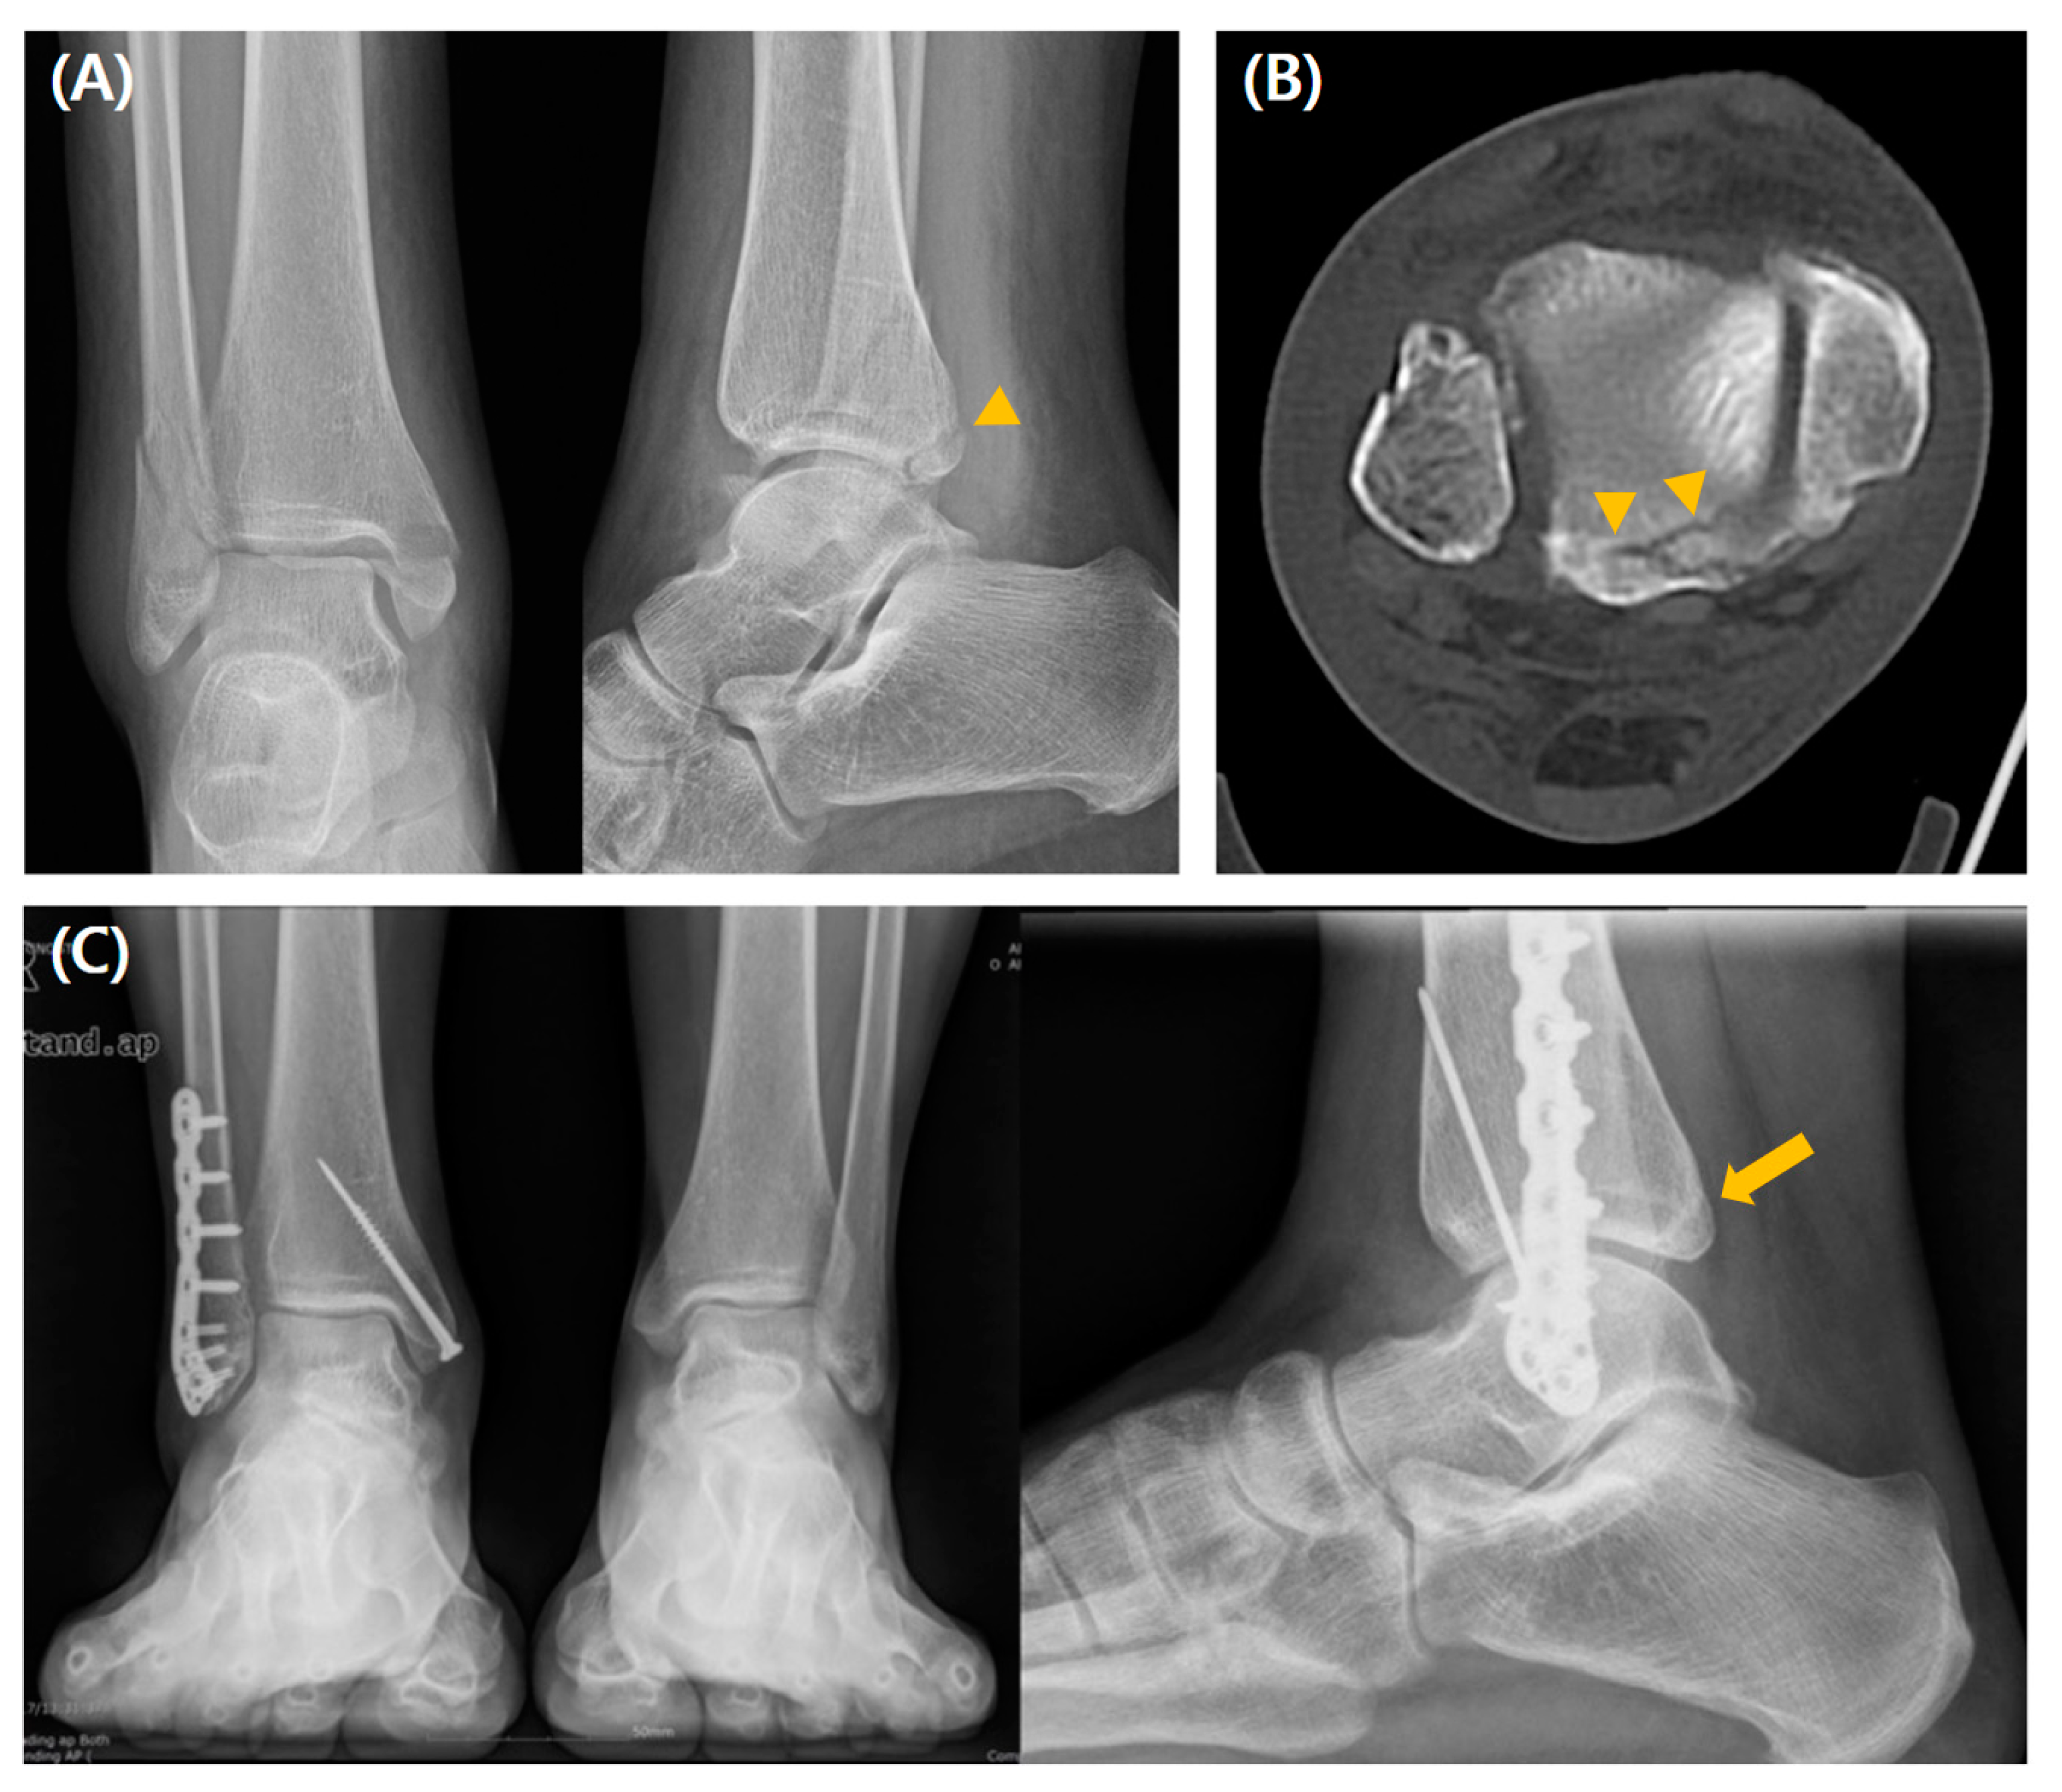

3.3. Comparison Between the Syndesmotic Stabilization and Nonstabilization Groups Within Type 3 Fracture

All patients with type 3 fractures underwent conservative PMF management; for concomitant syndesmotic instability, they underwent syndesmotic stabilization. At the final follow-up, there were no significant intergroup differences in radiological and clinical parameters, including the postoperative complications, with the numbers available (Table 4). A radiographic case example of a type 3 fracture is depicted in Figure 5.

The type 3 PMF mechanism has been considered a bony avulsion of the posterior inferior tibiofibular ligament (PITFL) caused by talus external rotation [16,17,19,44]. Therefore, it can be hypothesized that syndesmotic fixation restores ankle joint stability. According to our results, however, only 15 of the 36 patients with type 3 PMF required syndesmotic stabilization, which did not affect the radiological and clinical results. This is possible because the PITFL contributes to only 42% of the stability that the four component ligaments of the syndesmosis provide [45], and the syndesmotic instability assessed by intraoperative stress tests could be detected in the case of injury to two or more ligaments [18,37,43]. Therefore, we can assume that only PITFL injuries do not lead to clinical syndesmotic instability, and conservative management can be considered for type 3 PMF if syndesmotic instability is not detected in intraoperative stress tests. The concept that in pure PITFL avulsion fractures (type 3 PMF), only the restoration of the ankle’s lateral and medial components is enough to obtain stability and lead to satisfactory outcomes has been supported by several studies [11,12,14,19,21]. However, if syndesmosis instability is suspected, it may indicate PITFL avulsion accompanied by medial ligament injury or other associated damage. In such cases, careful evaluation is necessary to determine the need for syndesmosis fixation, medial ligament repair, and appropriate management of any additional injuries.

Figure 5. A case of a 34-year-old man who underwent conservative management without syndesmotic stabilization for type 3 PMF. (A) Preoperative radiographs show a small avulsion-type posterior lip fracture (arrowhead), and (B) preoperative CT scan images show a posterior malleolar fragment representing a type 3 fracture (arrowhead). (C) Weight-bearing radiographs obtained 2 years postoperatively show good reduction and bone healing (arrow).